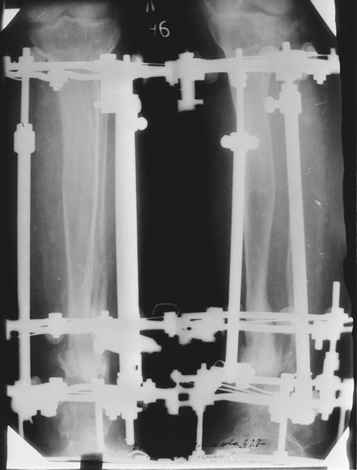

Случай, который я представляю, был сделан мной около 20 лет назад в Кургане.

Женщина 28 лет, пошедшая 13 предыдущих оперативных вмешательств по-поводу ВПБ имела 9 см. укорочения.

На первом этапе аппаратом Илизарова закрыто устранена деформация голени.

На втором этапе произведёно освежение краёв костных фрагментов б/б и м/б костей с приданием проксимальному фрагменту б/б кости впалой, а дистальному выпуклой формы, открытие канала проксимального фрагмента и погружной остеосинтез, а также остеотомия б/б кости в в/3 и м/б кости на границе с/3 и н/3 голени. Больной проводился одновременный бифокальный компрессионно-дистракционный остеосинтез. Достигнуто 11 см. удлинение и сращение ВПГ.

Срок лечения 11 месяцев. Наблюдение 2 года.